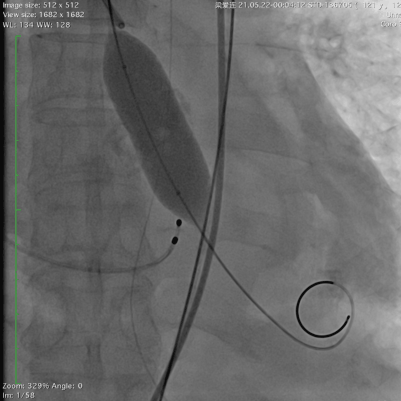

78岁的阿婆,入院3年余前出现活动后胸闷,气促。3天前出现恶心,呕吐,双下肢水肿,来广东省人民医院急诊科就诊,行心脏彩超提示为重度主动脉瓣狭窄并中度关闭不全,经郭惠明主任团队评估后收住入院,拟行TAVR治疗,阿婆急性心衰,呼吸急促,循环不稳,我院ICU团队立刻对患者进行抢救处理,紧急气管插管,循环不稳定,大剂量血管活性药物维持,尿少,乳酸持续升高,命悬一线。郭惠明刘健主任团队立刻对患者施行紧急救治,23点40麻醉,00:30开始手术,01:27分手术结束,整个手术过程持续不到1小时。